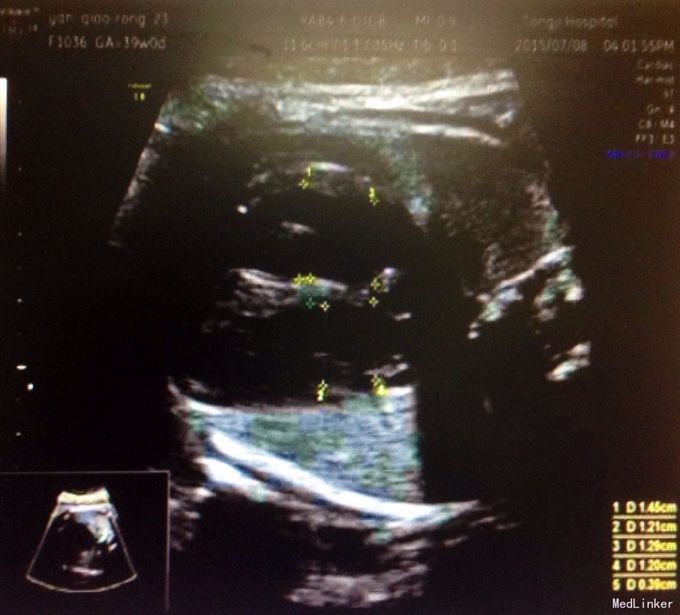

体检:生命体征正常,全身皮肤黏膜无黄染,腹隆,肝脾肋下未及,宫高29,腹围88, FHR148,头位,未触及宫缩,未行内诊,骨盆外测量22-26-18-8 辅助检查:2周前外院检测总胆汁酸25umol/L,一周前复查总胆汁酸60umol/L,今日外 院B超示晚孕,单活胎,头位,胎儿房间隔中部囊样无回声,考虑膨胀瘤可能,本院检查 结果如下图